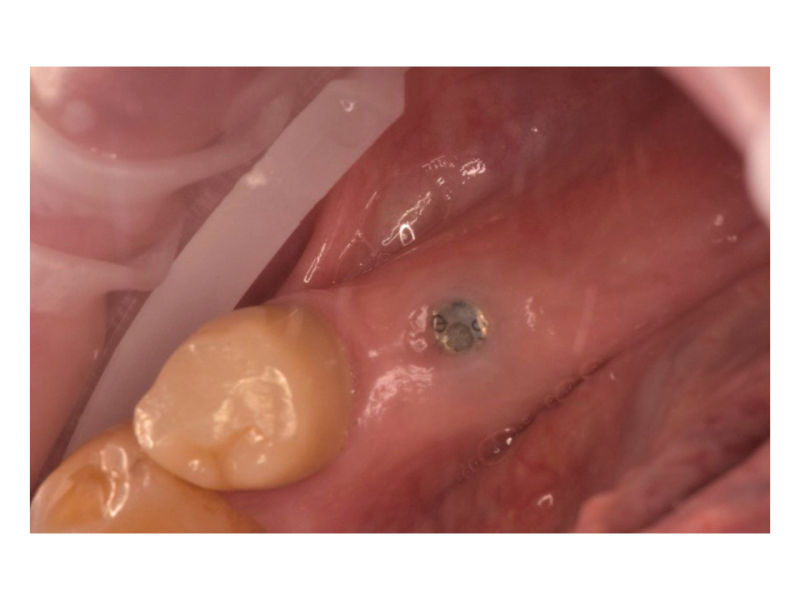

Установка импланта Dentium

Пациент обратился в клинику с целью восстановления жевательных зубов на нижней челюсти слева. Рассматривался вариант протезирования с опорой на имплантаты для обеспечения надёжности и долговечности конструкции. Проведена диагностика и выбрана тактика имплантации. Установлены два имплантата Dentium в области 35 и 37 зубов. Через 3 месяца после остеоинтеграции: заменён формирователь десны на имплантате 35 и установлен формирователь десны на имплантате 37. Пациент направлен к стоматологу-ортопеду для изготовления постоянных ортопедических конструкций

Доктор: Шарифуллин Айнур Азатович